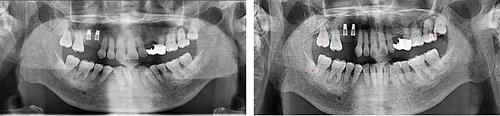

術后13個月